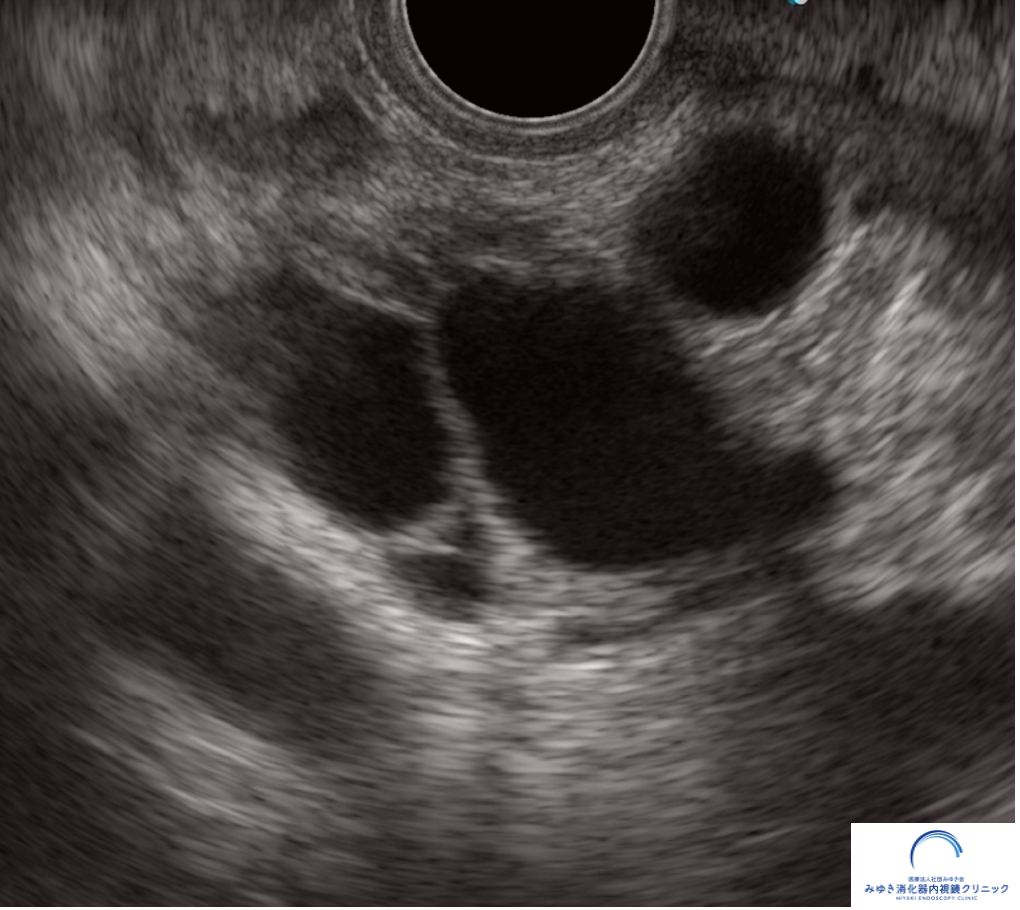

超音波内視鏡(EUS)は、内視鏡の先端についた超音波装置で、胃や十二指腸の内側から膵臓をすぐ近くで観察する検査です。

お腹の上から行う腹部エコーでは見えにくい膵臓も、EUSではより詳しく観察できるため、IPMNの評価や小さな膵がんの発見に役立つことがあります。

実際の検査では、IPMNはこのように観察されます。

超音波内視鏡(EUS)では、膵嚢胞の内部や壁の状態まで詳しく観察することができます